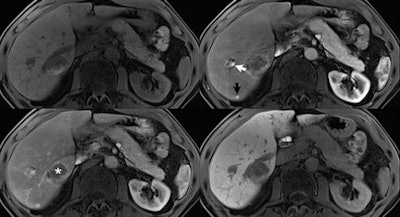

Application of an ultrashort breath-hold Dixon VIBE sequence for improved arterial phase imaging, with resultant overall improved image quality due to better patient compliance. Precontrast (top left), first (top right), and third (bottom left) arterial phase images, and 20-minute delayed hepatocellular phase images (bottom right) after injection of gadoxetic acid are presented in a 74-year-old man with metastatic rectal adenocarcinoma. Acquisition time for each image series was 4.8 seconds, with scans acquired at 3-tesla using a 60-channel body coil. A new small metastasis along the dorsal margin of the liver (black arrow) demonstrates prominent early arterial enhancement, with some wash out by the late arterial image, and no uptake in the delayed phase. Also visualized at this level are a hemangioma (white arrow) and a larger metastasis previously treated by microwave ablation (asterisk). Note the absence of respiratory artifacts due primarily to the short scan time, as compared with more conventional 15 to 20 seconds VIBE acquisitions.Application of an ultrashort breath-hold Dixon VIBE sequence for improved arterial phase imaging, with resultant overall improved image quality due to better patient compliance. Precontrast (top left), first (top right), and third (bottom left) arterial phase images, and 20-minute delayed hepatocellular phase images (bottom right) after injection of gadoxetic acid are presented in a 74-year-old man with metastatic rectal adenocarcinoma. Acquisition time for each image series was 4.8 seconds, with scans acquired at 3-tesla using a 60-channel body coil. A new small metastasis along the dorsal margin of the liver (black arrow) demonstrates prominent early arterial enhancement, with some wash out by the late arterial image, and no uptake in the delayed phase. Also visualized at this level are a hemangioma (white arrow) and a larger metastasis previously treated by microwave ablation (asterisk). Note the absence of respiratory artifacts due primarily to the short scan time, as compared with more conventional 15 to 20 seconds VIBE acquisitions.